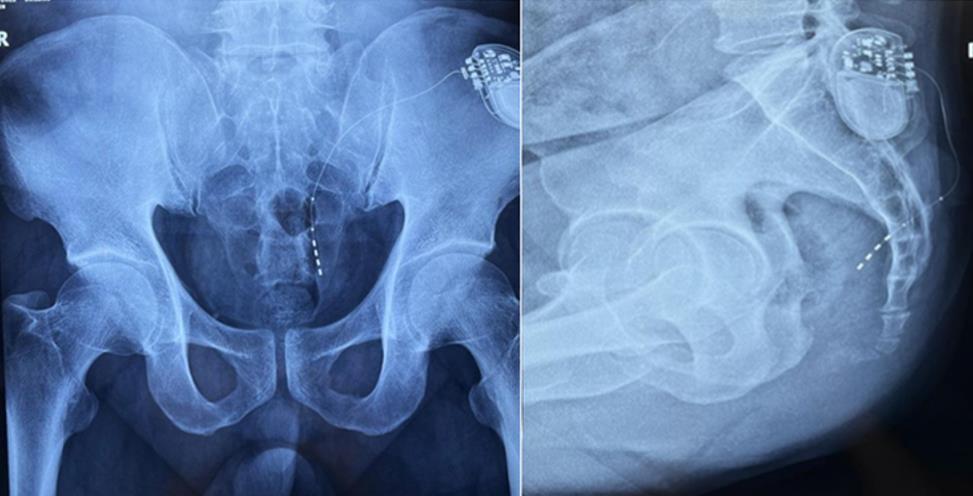

該患者兩年前被診斷患有膀胱過度活動癥(OAB),出現嚴重尿頻、尿急、尿細線等癥狀,醫生為其做了骶神經調控手術。近期,患者癥狀又開始加重,生活質量受到影響,為減輕癥狀,改善生活,患者前往南醫大二附院就診。衛中慶主任及其團隊在查看患者病情后,決定重新調整電極刺激位置,將刺激點由原左側骶4神經孔改為骶3神經孔,通過新的神經調節順利地改善了癥狀。

患者術前影像